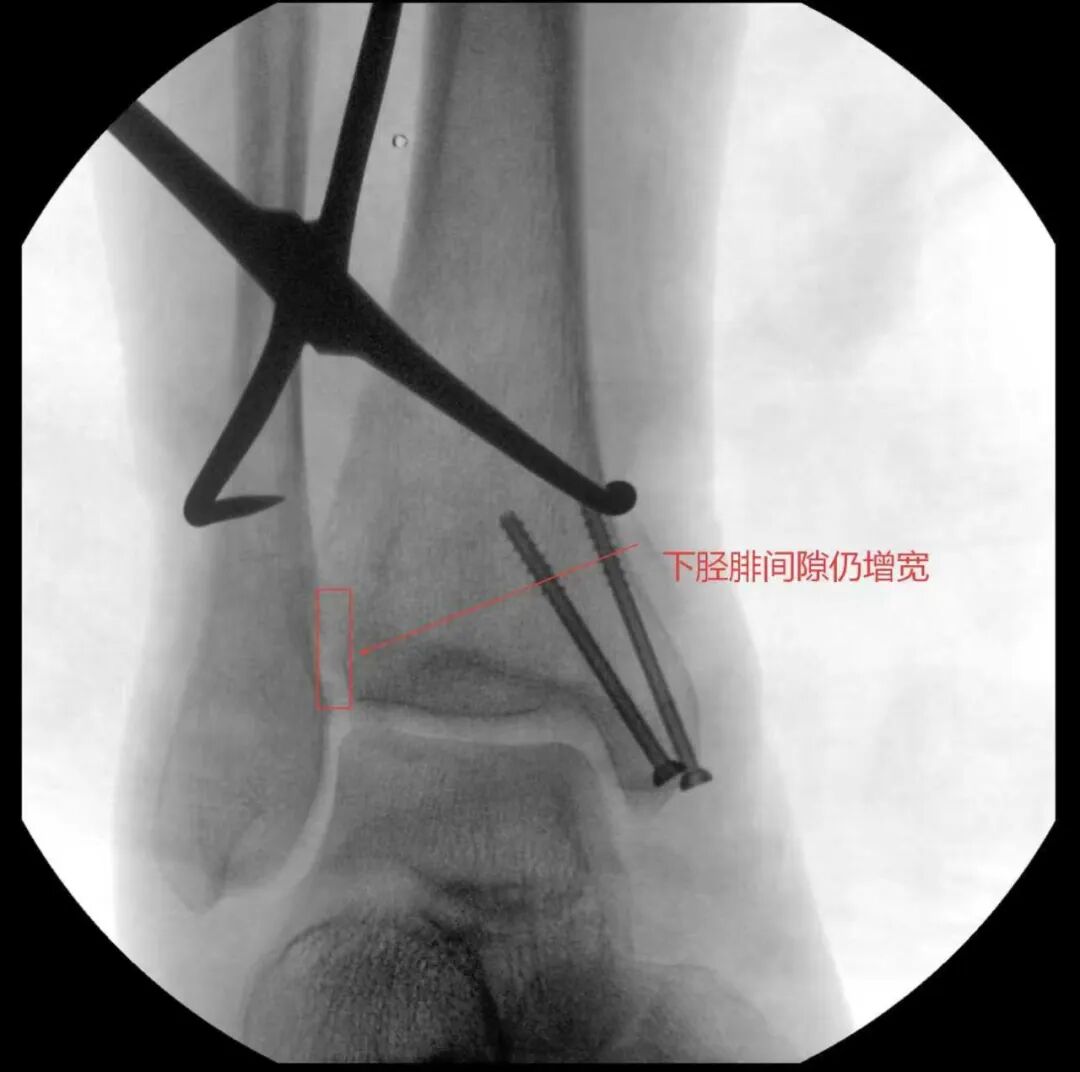

术中进行下胫腓拉力试验结果呈明显阳性,且复位效果未达预期,团队当机立断决定切开探查,发现前结节骨折块嵌顿于下胫腓间隙,正是阻碍复位的关键,取出骨折块后顺利完成复位,手术按规范流程顺利结束。